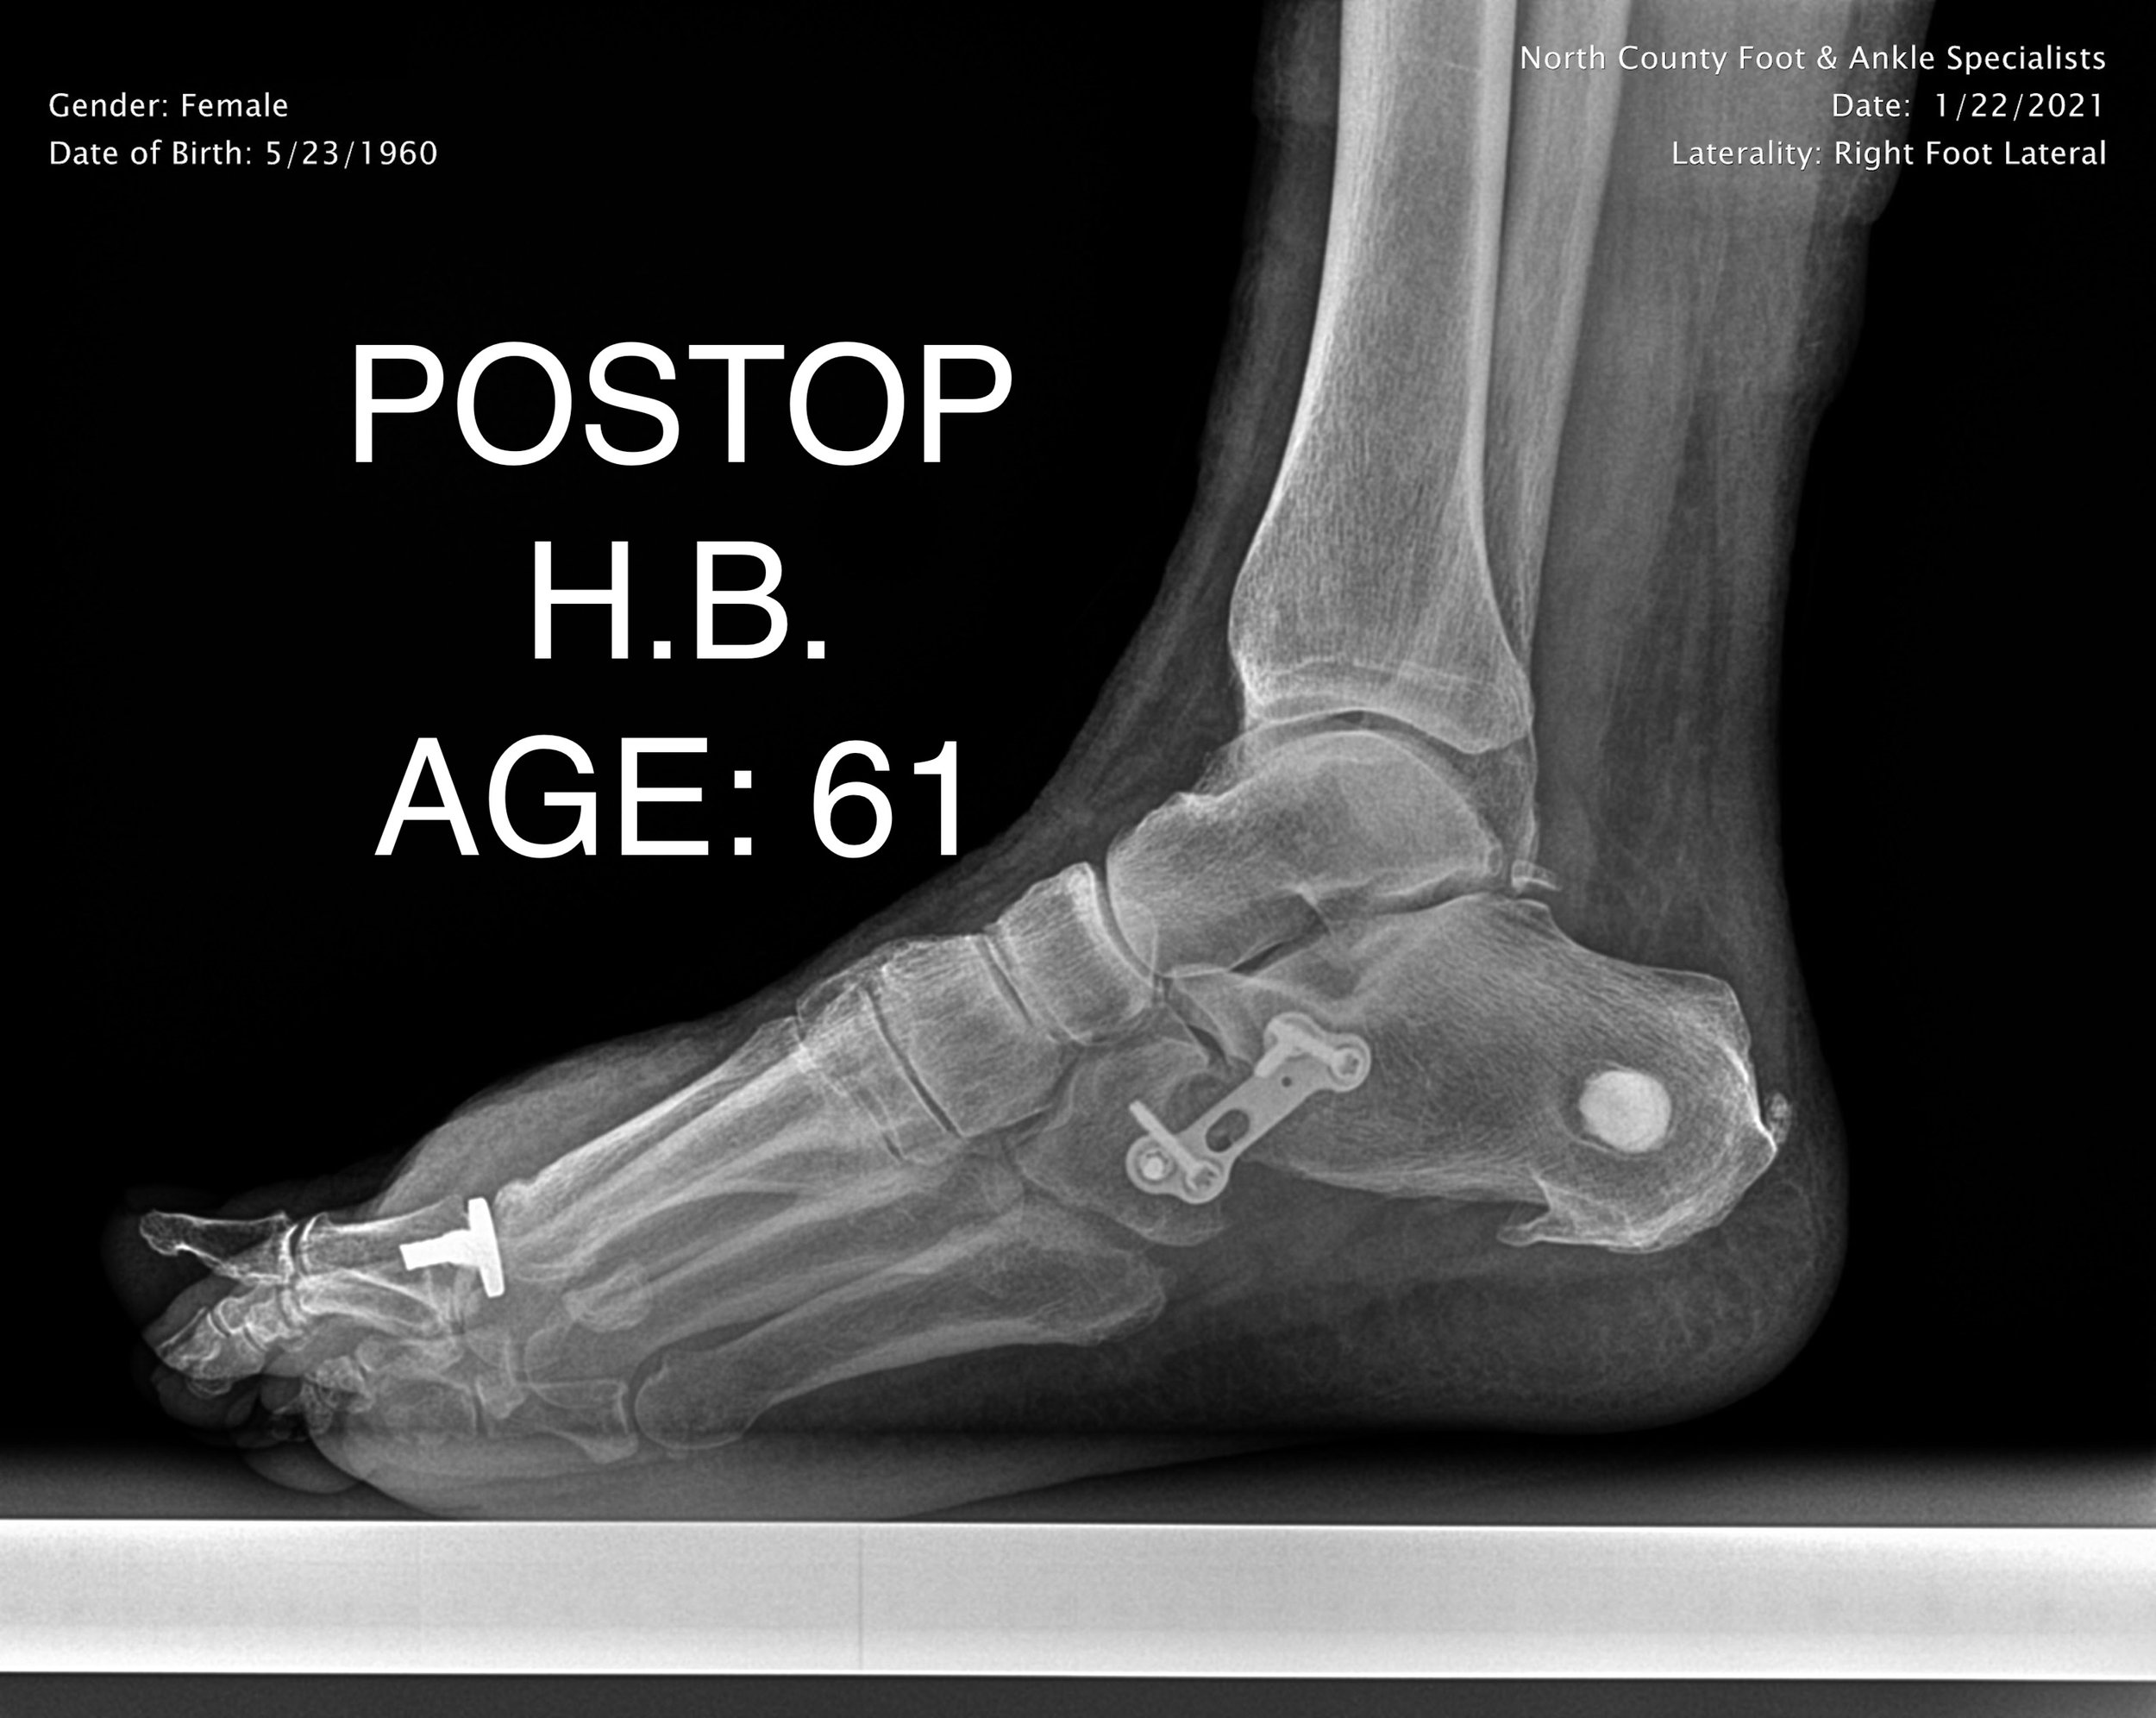

ADULT FLAT FOOT RECON